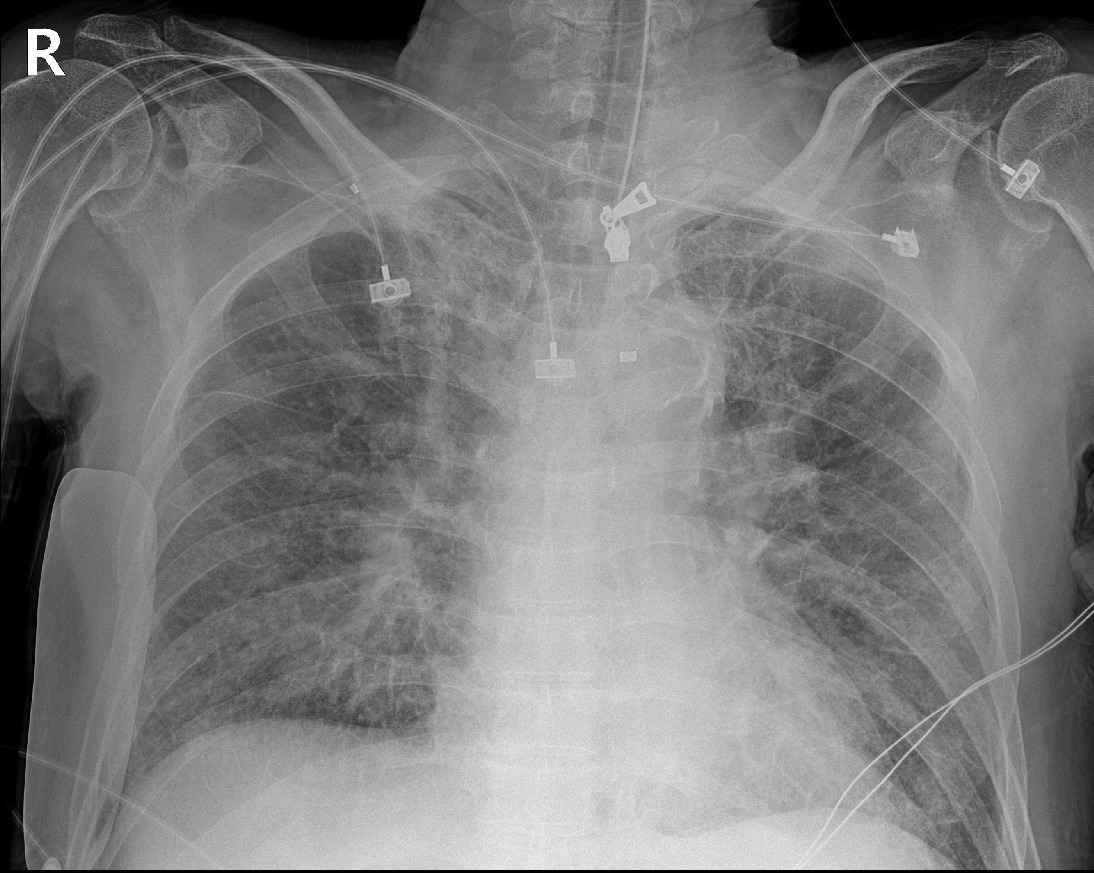

오자마자 환자 재운뒤 기관 삽관 후에 인공호흡기 걸어놓고 엑스레이 찍어보니 급성폐부종이 확인됩니다.

심전도 찍어보니 V1~4 ST elevation, II III aVF ST depression

초음파 갖다 대보니 좌심실 첨단부 아예 안 움직임. 전형적인 심근경색을 나타내는 검사결과입니다.